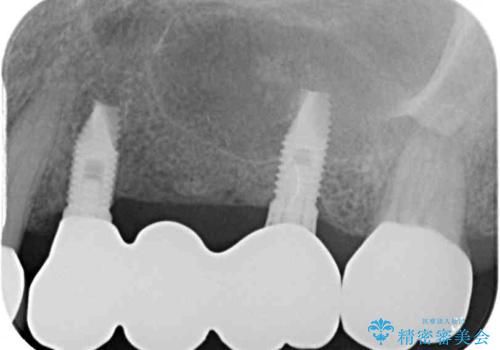

インプラントを埋入するために必要な骨の高さがなかったため、上顎洞底の粘膜を挙上しました。

手術後は処置部に痣や腫脹が出現したり、痛みが出たりしましたが、補綴治療後は咬み合わせが安定し、大変満足していただきました。